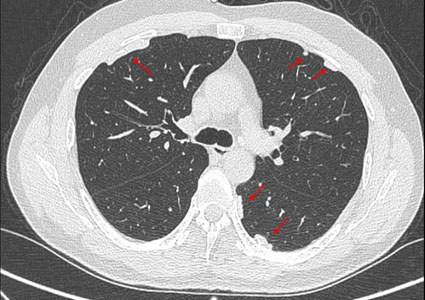

Tomografía computarizada (TC) de tórax: La TC de tórax es una técnica de imagen más precisa que puede mostrar con mayor detalle las alteraciones pleurales, como engrosamiento, calcificaciones, masas o derrame pleural (Figuras 4, 5 y 6).

Frente a la presencia de alteraciones pleurales en la Radiografía de tórax con técnica OIT y confirmadas con tomografía computarizada de tórax de alta resolución sin contraste (TCAR), será de vital importancia realizar el diagnóstico diferencial sobre alteraciones pleurales asociadas a la exposición al amianto (Figuras 2, 3, 4 y 5). Entre las patologías diferenciales se incluyen: 53

Engrosamiento pleural difuso: Se produce como resultado de la fibrosis de la pleura visceral, a menudo bilateralmente, 59 y es considerablemente menos común que las placas pleurales. Requiere una exposición a mayores cantidades de fibras de amianto para desarrollarse. La detección se realiza mediante tomografía axial computarizada de tórax, y se observa un engrosamiento de bordes irregulares y mal definidos que se extiende por más de cuatro espacios intercostales. Por lo general, el engrosamiento pleural difuso se extiende hacia arriba a lo largo de la pared torácica lateral y se registra solo en presencia de un ángulo costo frénico obliterado continuo. Las lesiones raramente se calcifican. Una de las características del engrosamiento pleural difuso es que produce alteraciones funcionales restrictivas sin afectar el parénquima pulmonar subyacente. 60

Atelectasias redondas: Es una anormalidad poco común de la pleura que se pliega sobre sí misma, atrapando el tejido pulmonar adyacente y dando lugar a la formación de una imagen curva en los bronquios y vasos sanguíneos que se dirigen hacia esa zona, lo que se conoce radiológicamente como "cola de cometa". 61 Aunque teóricamente puede verse en la fibrosis pleural de cualquier origen, en la práctica la mayoría de los casos están asociados a la exposición a fibras de amianto. En la tomografía axial computarizada de tórax, se identifica por tres signos radiológicos característicos: una masa redonda u ovalada de 2.5 a 7 cm que contacta la superficie pleural, la presencia de una estructura lineal en forma de cola en su interior correspondiente a los elementos broncovasculares y el engrosamiento de la pleura subyacente. 62 Es importante distinguir una atelectasia redonda de un carcinoma broncogénico, ya que su apariencia en la imagen puede ser similar.